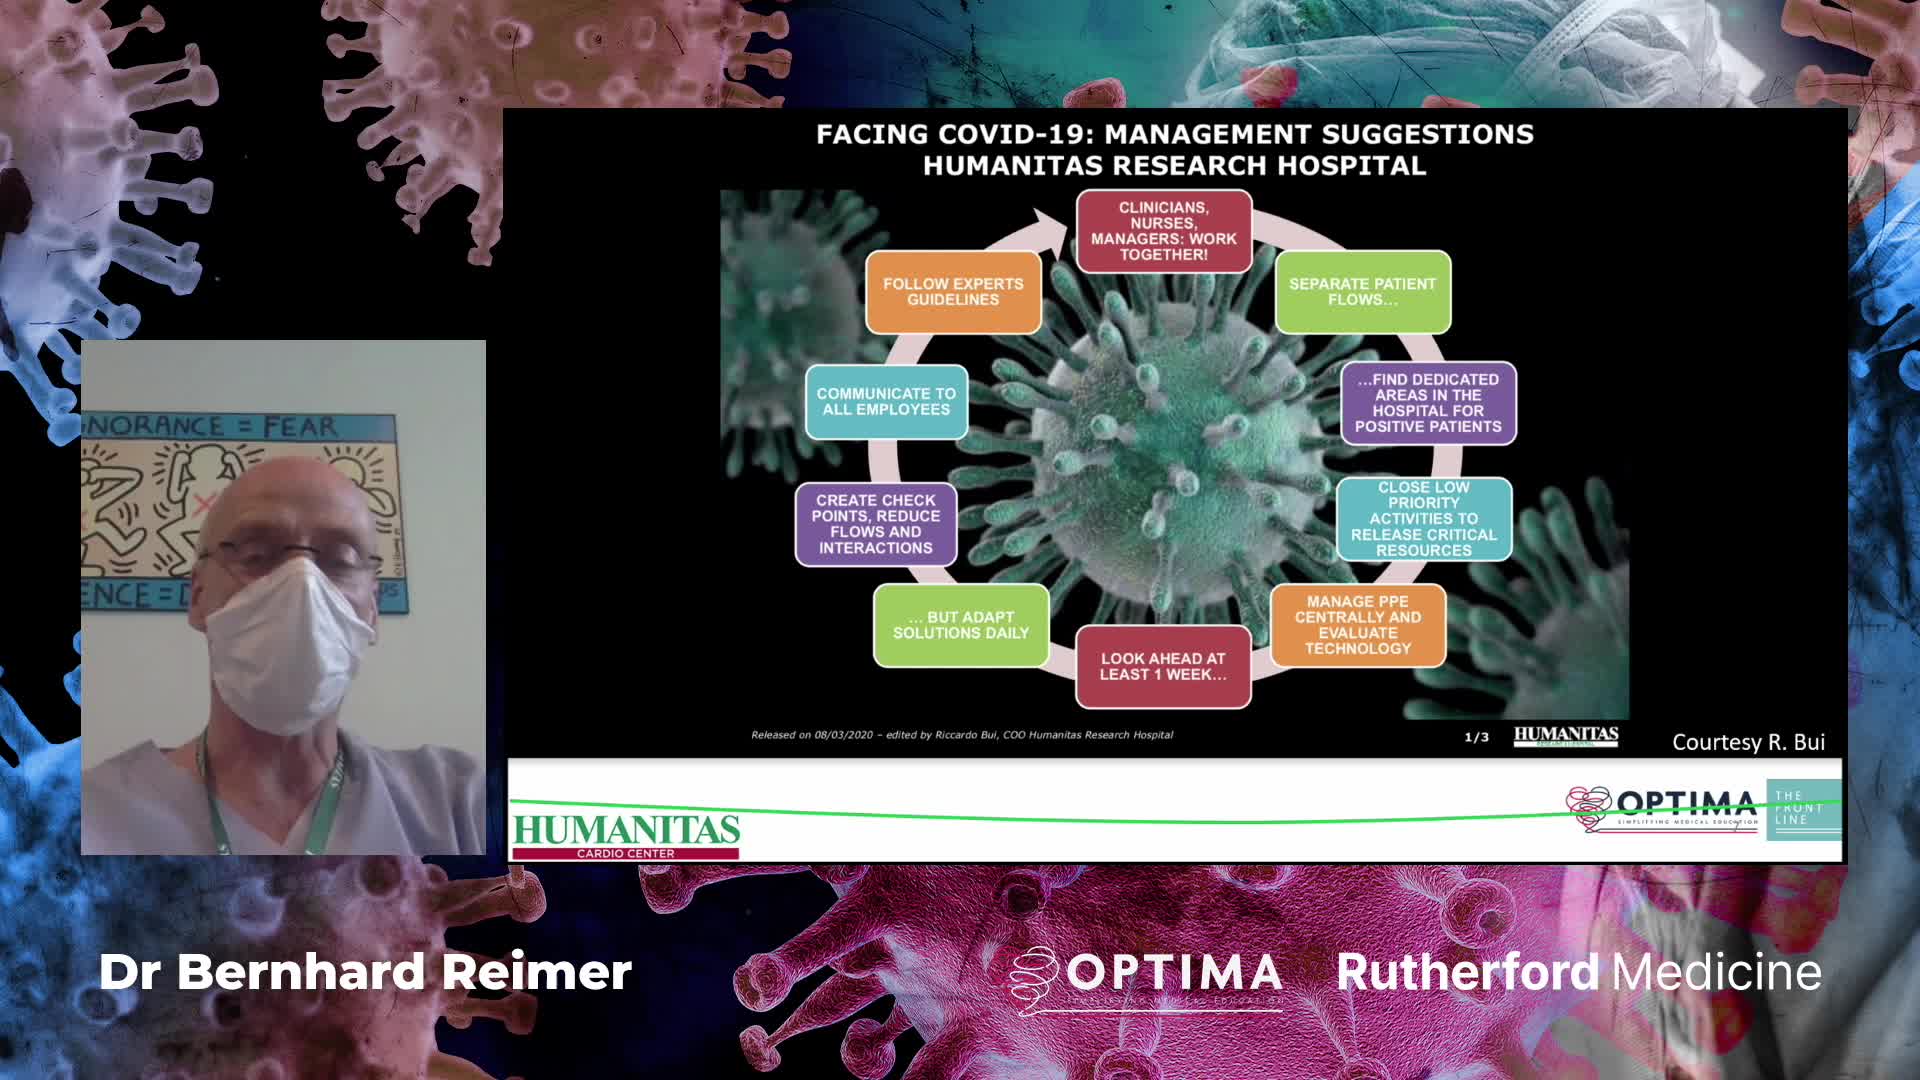

Past Courses: COVID-19

COVID-19: The Front Line. The Role of Extra Corporeal Membrane Oxygenation (ECMO) in the treatment of severe COVID-19